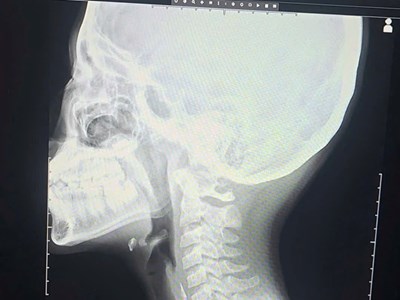

Trước đó, ngày 21.7, bệnh nhi vào viện cấp cứu trong tình trạng đau bụng từng cơn dữ dội vùng thượng vị kèm nôn khan, chướng bụng tăng dần. Qua thăm khám, siêu âm ổ bụng, chụp X-quang, bác sĩ chẩn đoán cháu bị xoắn dạ dày và chỉ định mổ cấp cứu.